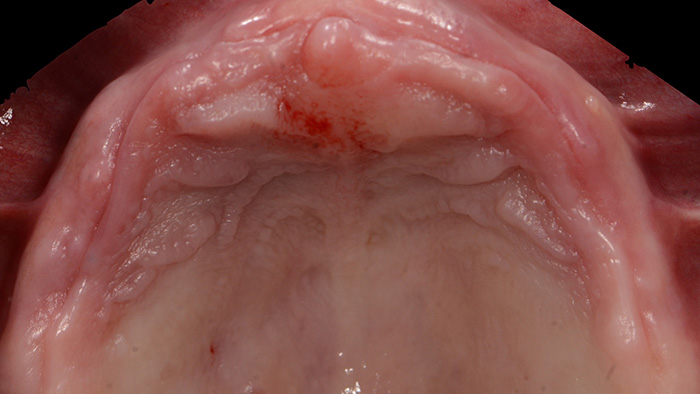

Fig. 3 : Vue occlusale du maxillaire édenté.